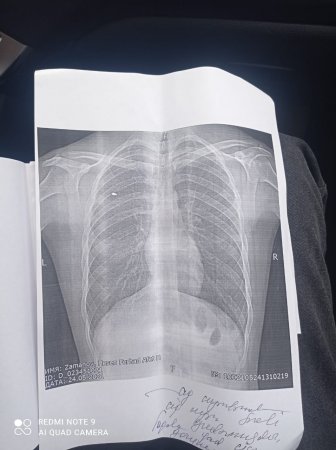

İmişli Rayon Qızılkənd kənd sakini Zamanov Həsən Fərhad oğlu 44 günlük Vətən savaşı iştirakçısıdır. Mediatv.az bildirir ki, o da bu gün Əmək və Əhalinin Sosial Müdafiəsi Nazirliyindən şikayətçidir.Qarabağ Qazisinin redaksiyamıza ünvanladığı müraciəti təqdim edirik: "Mən 44 günlük Vətən müharibəsinin könüllü qazisiyəm. Ağciyərimdən (qarşıq tipli əhəmiyətli ventelsasiya pozguntusu) ilə yaralanmışam. Partlayış "travma"sı olub. Üzvü emosianal labil pozuntusu, şəxsiyət pozuntusu, üzvü disseosativ pozuntusu ilə 14B, 83B maddəsinə əsasən diaqnoz qoyulub.

Amma çox təəssüf ki bugünə kimi əlilliymi təyin edilmir".